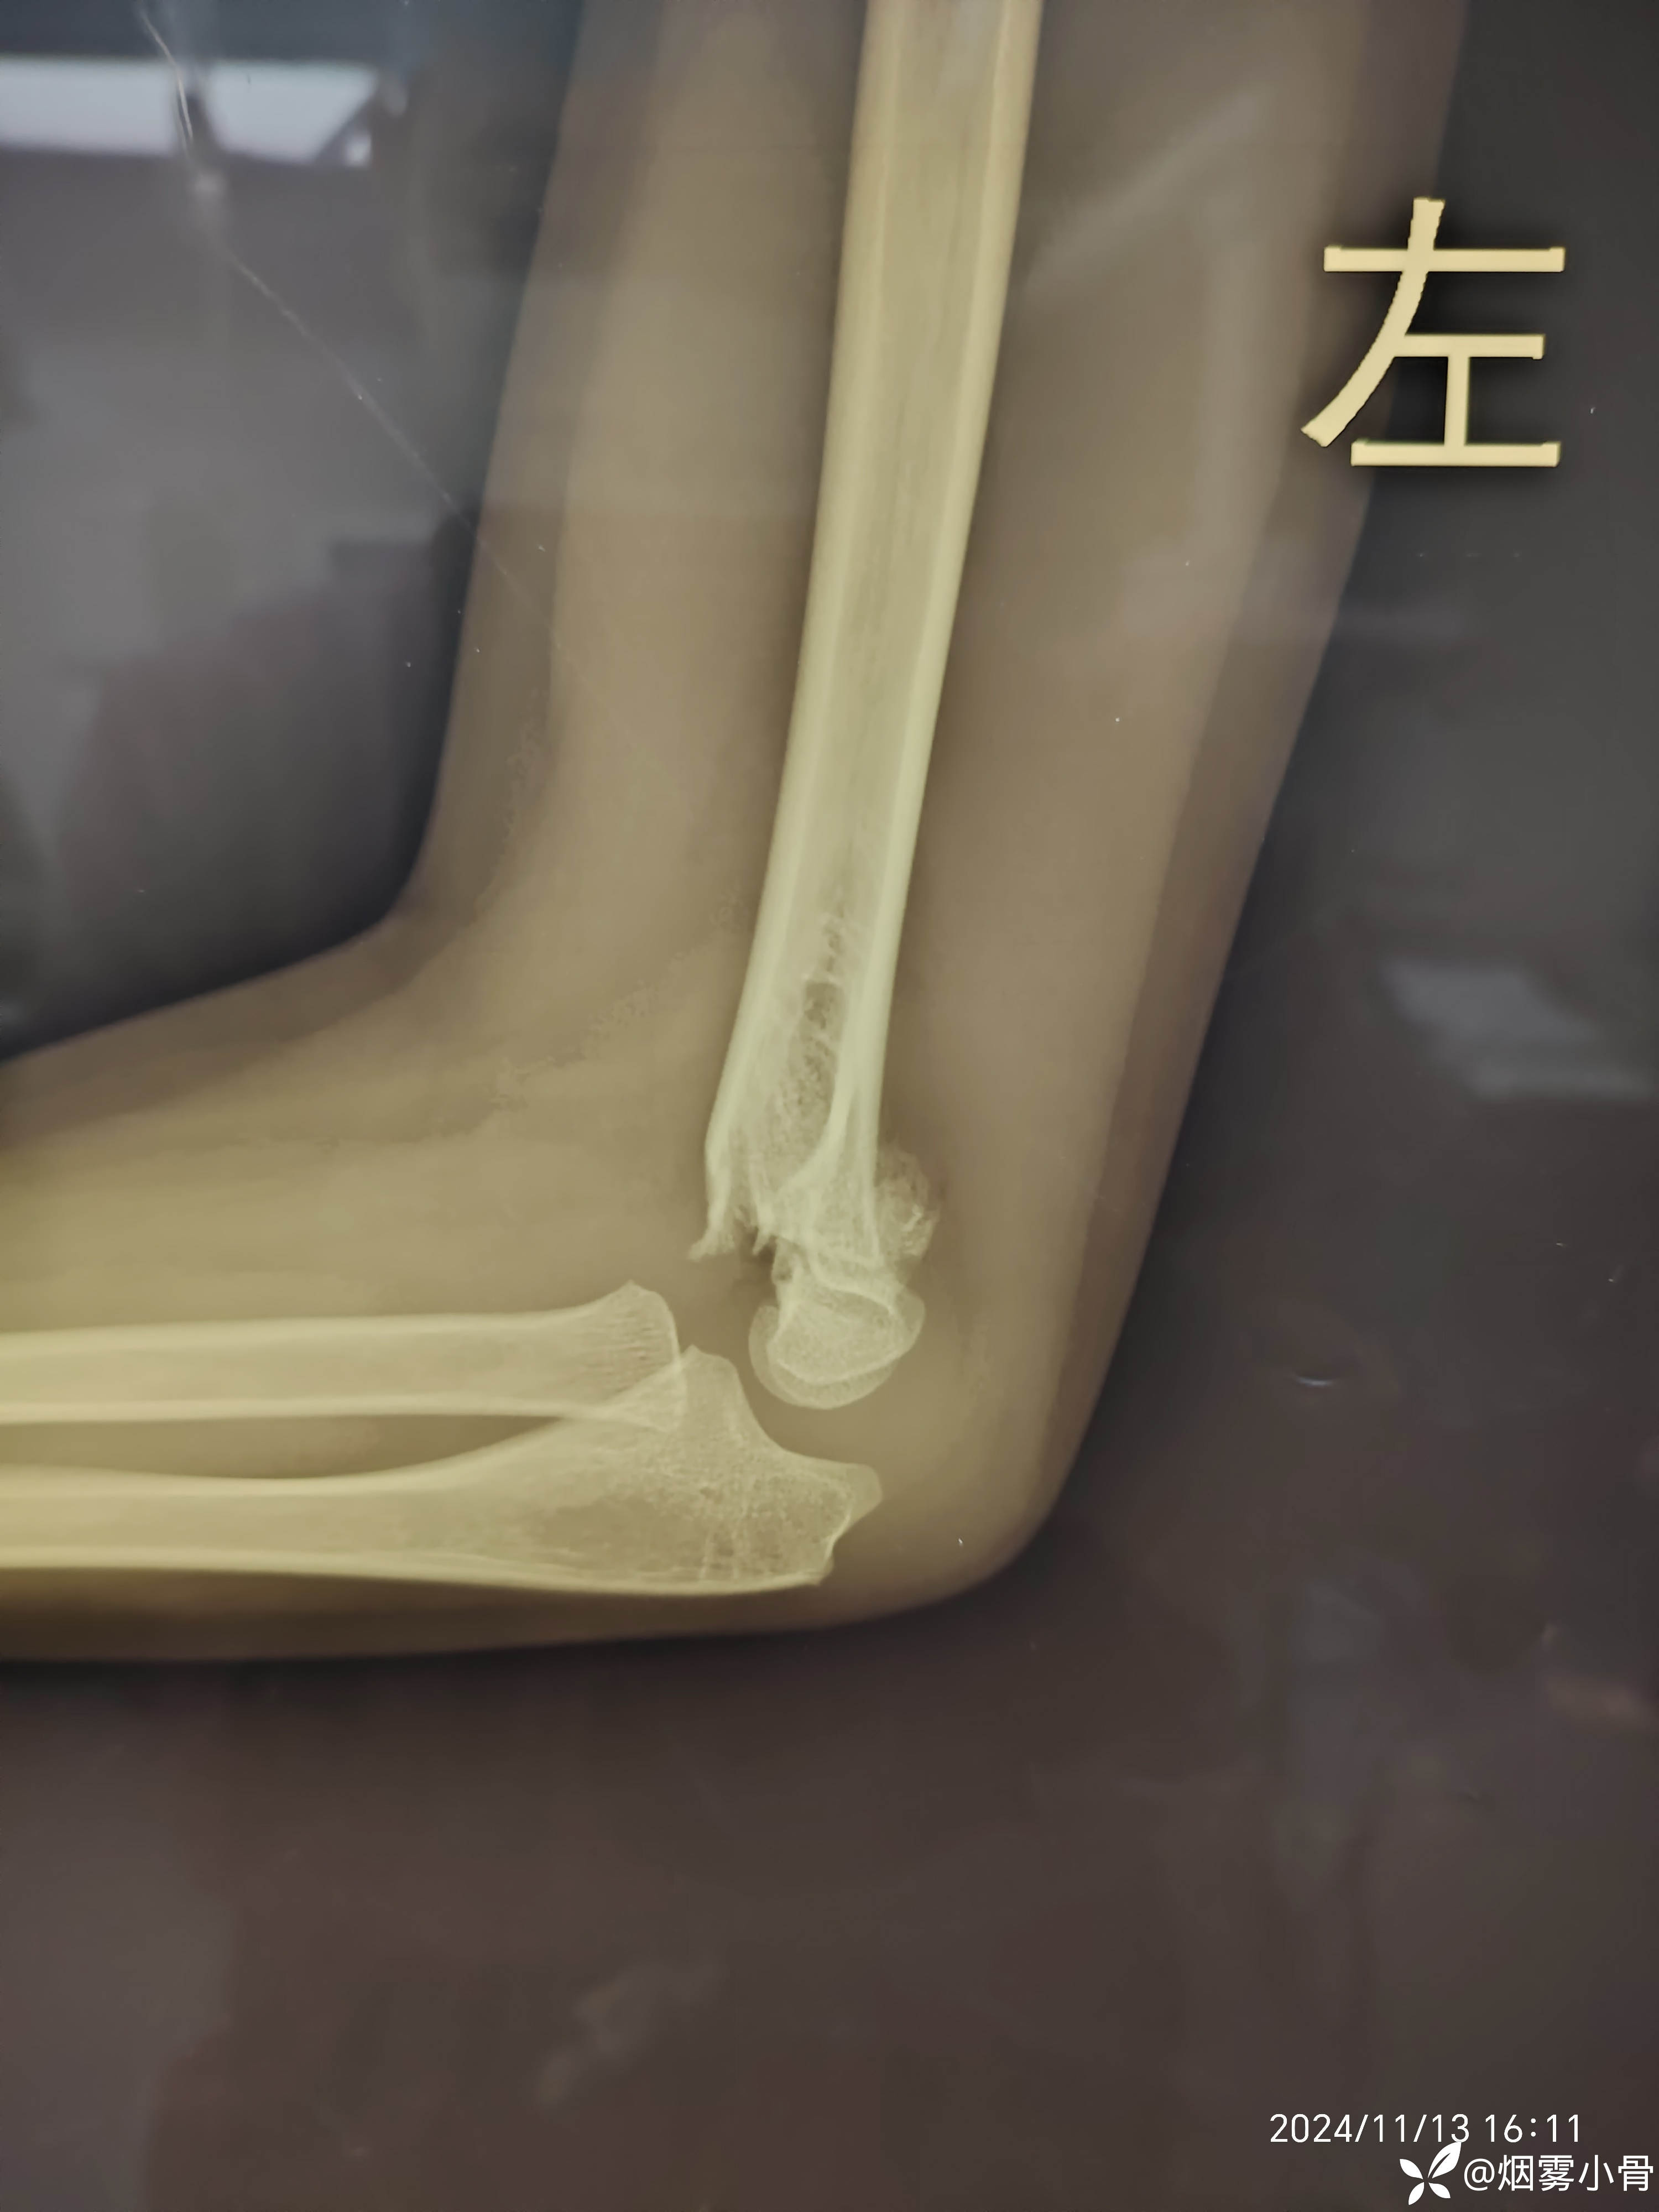

6岁肱骨髁上骨折,急诊30分钟完成零切开闭合复位克氏针内固定

【临床诊断】:左肱骨髁上骨折